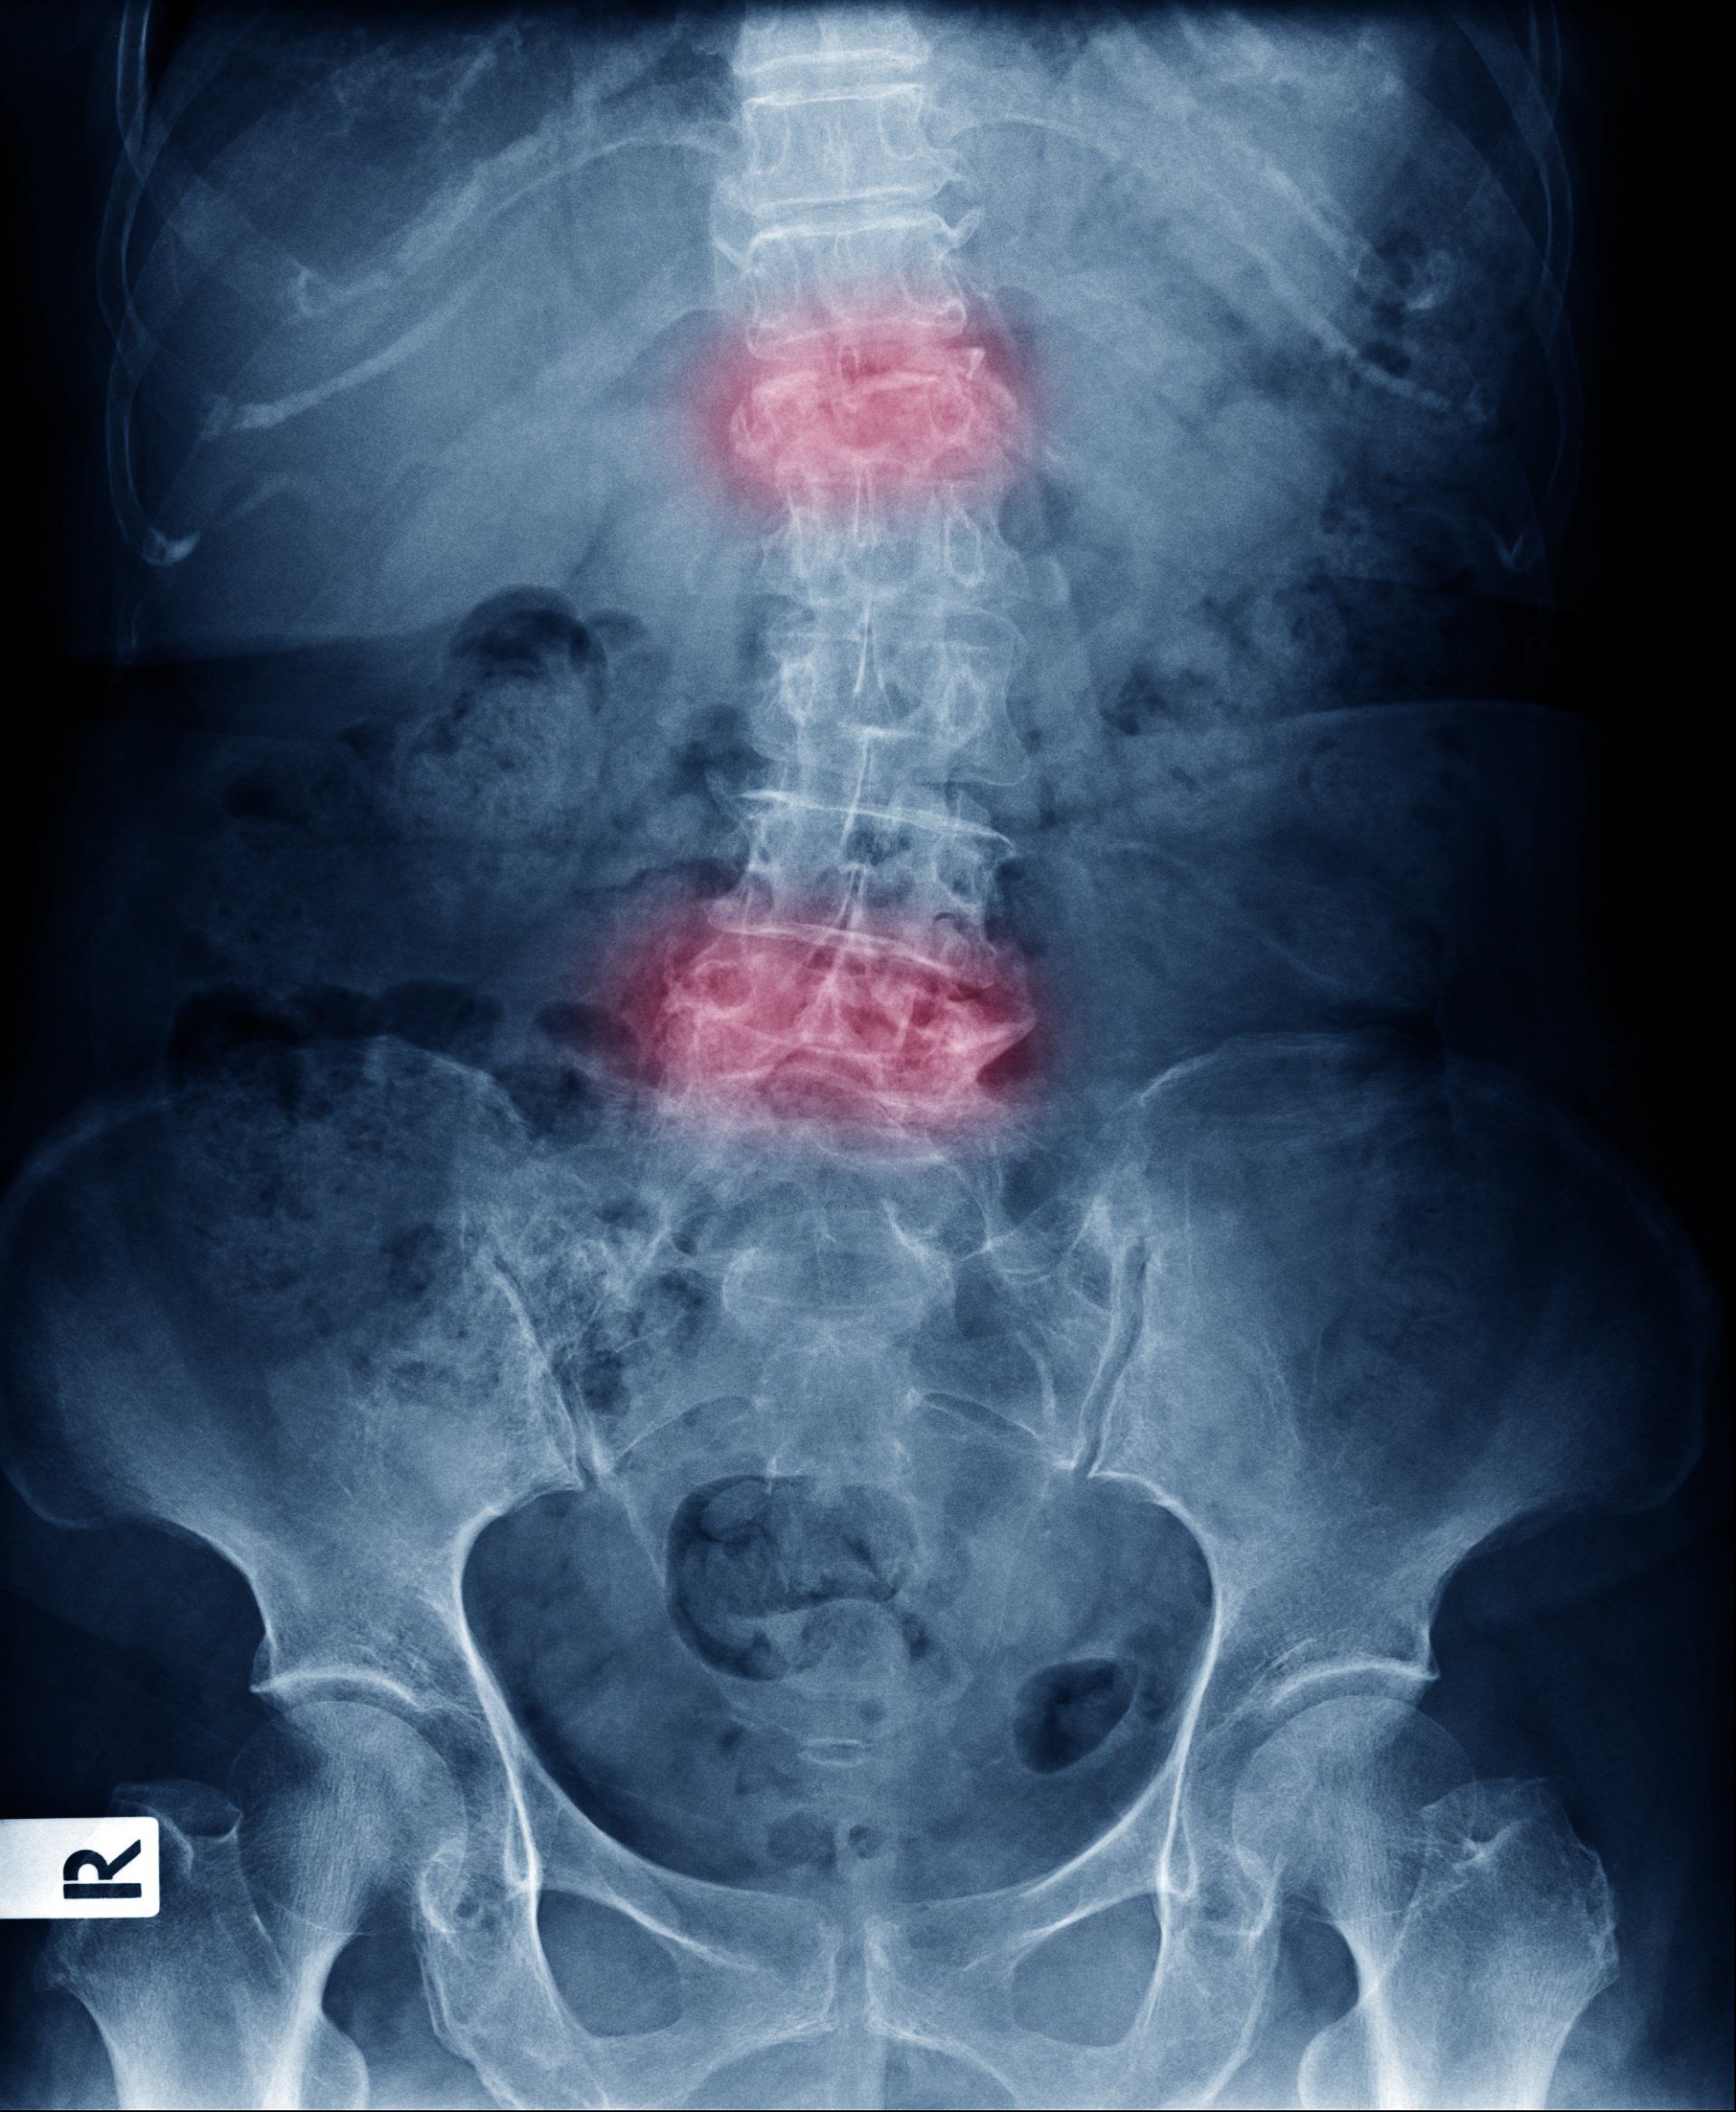

Doenças da Coluna Vertebral